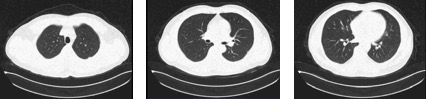

胸部CT

右肺中叶及左肺上叶尖后段少许感染。

右肺中叶及左肺上叶尖后段纤维条索影。

左肺下叶外基底段小结节影:炎性结节?请随访。

肺中叶及左肺上叶少许纤维条索。

上述表现比较2017-04-26CT无明显变化。